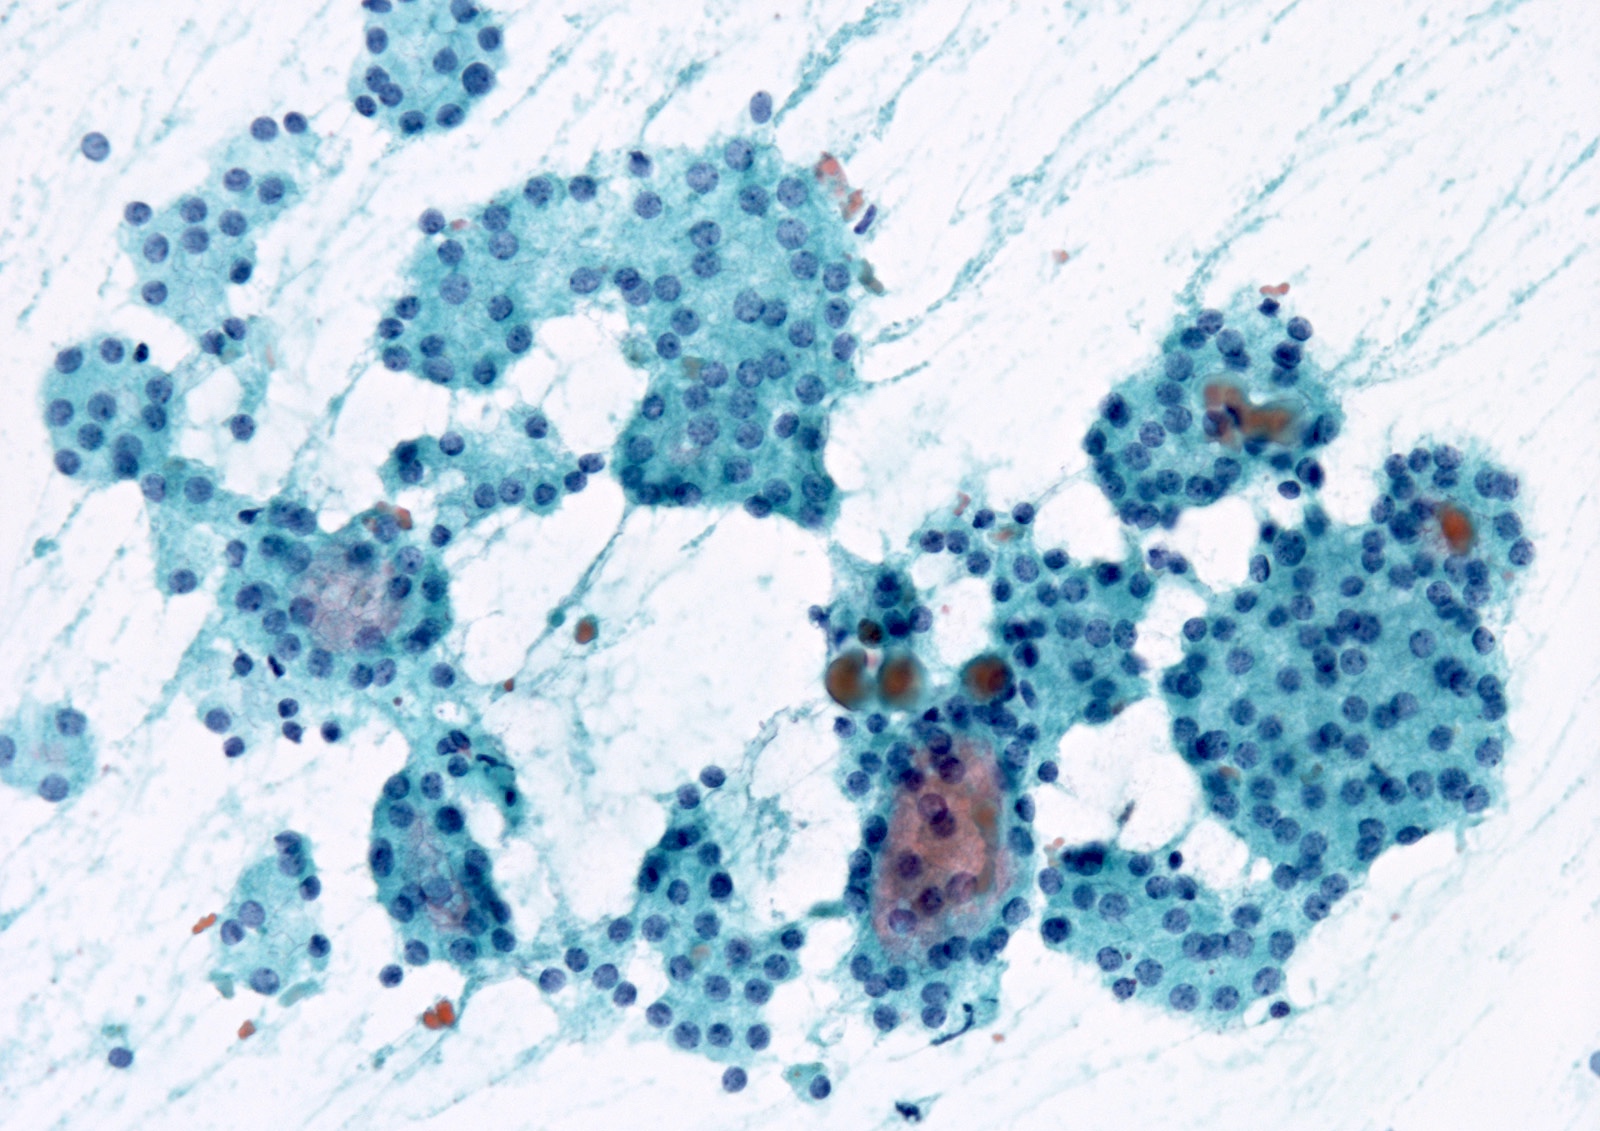

Cytology images

Contributed by Ayana Suzuki, Ph.D.

- Architectural atypia:

- Rare clusters with microfollicles or crowded 3 dimensional groups with scant colloid

- 50 - 70% of follicular cells exhibit microfollicles but without a marked predominance

- Focally prominent microfollicles with minimal nuclear atypia

- More prominent than usual population of microfollicles but not sufficient for a diagnosis of follicular neoplasm